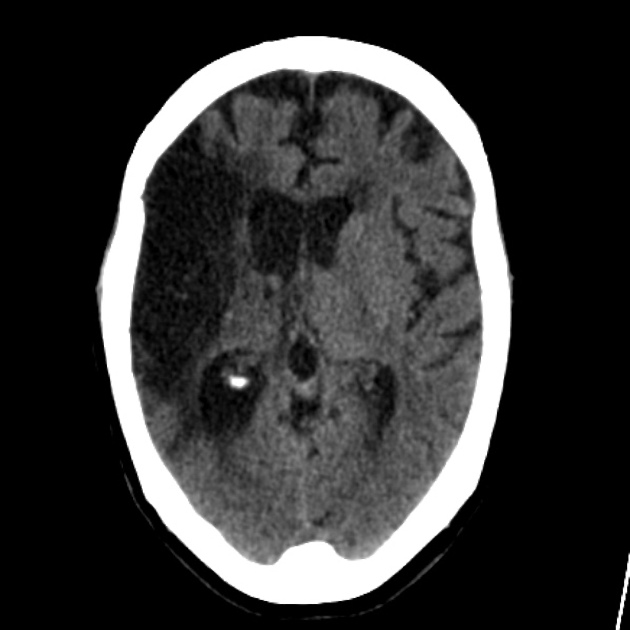

Image Neuronal progenitors of the dentate gyrus express the SARS-CoV-2 cell receptor during migration in the developing human hippocampus pubmed.ncbi.nlm.nih.gov/37149825/